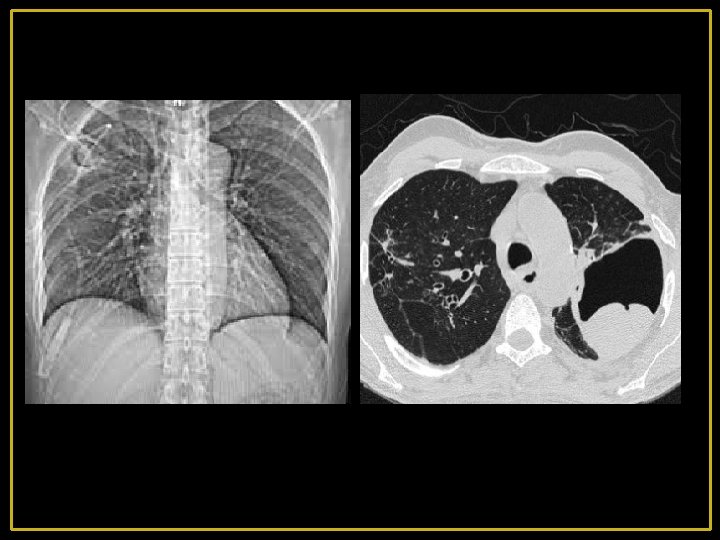

- La cavitation est fréquente - Les cavités sont le plus souvent multiples, elles peuvent être isolées ou se développer dans une plage de condensation alvéolaire - l’association à d'autres lésions du parenchyme pulmonaire en particulier micronodulaires est très évocatrices du diagnostic - L'atteinte prédomine au niveau des lobes supérieurs et dans les segments apicaux des lobes inférieurs - La paroi est d’aspect variable : régulière ou épaisse et nodulaire - Contenu : aérique ou hydro-aérique